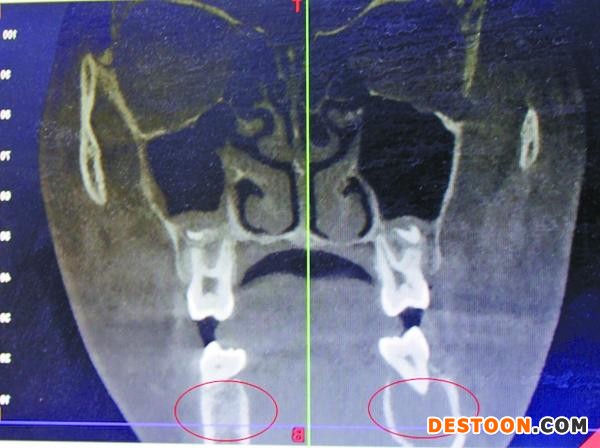

受血管瘤影響,右頜骨發(fā)生病變

據(jù)口腔醫(yī)院醫(yī)生王琨介紹,4月7日,在采取措施止血后,院方迅速為小玉進行了一系列檢查,發(fā)現(xiàn)其患的是一種非常罕見的頜骨中央性血管瘤。“下牙槽里的動脈血管發(fā)生病變,長了若干細微的支血管,將她的頜骨破壞后發(fā)生出血。”

宋慶高博士說,受血管瘤病變影響,女孩的右頜骨,已經(jīng)形成8×2.5厘米大小的腔竇,“相當于一個空洞。”從方便手術考慮,完全可能將她右側頜骨去掉,但那樣會形成面部缺陷,影響美觀,而且右側無法長牙。